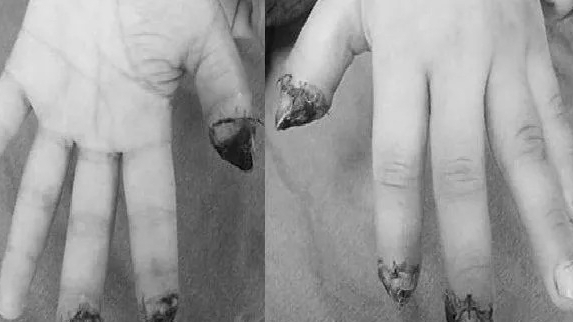

Theo BS. CKI Lê Anh Tú khoa Chấn thương Chung và Vi phẫu (B1), Bệnh viện Quân y 103, trước đó, ngày 24/9/2023, đơn vị đã tiếp nhận bệnh nhân N.V.Đ (30 tuổi) bị đứt rời 3 ngón tay gồm ngón trỏ, ngón giữa và ngón nhẫn do tai nạn lao động. Bệnh nhân bị máy dập nhựa cắt và dập vào bàn tay phải.

| Hình ảnh bàn tay của bệnh nhân được các bác sĩ phẫu thuật nối lại thành công |

Ca mổ diễn ra trong đêm, sau 4 tiếng các ngón tay bị đứt rời đã được nối lại thành công. Hiện tại, vết mổ của bệnh nhân đang liền, các ngón tay đã sống tốt và đang trong quá trình hồi phục.